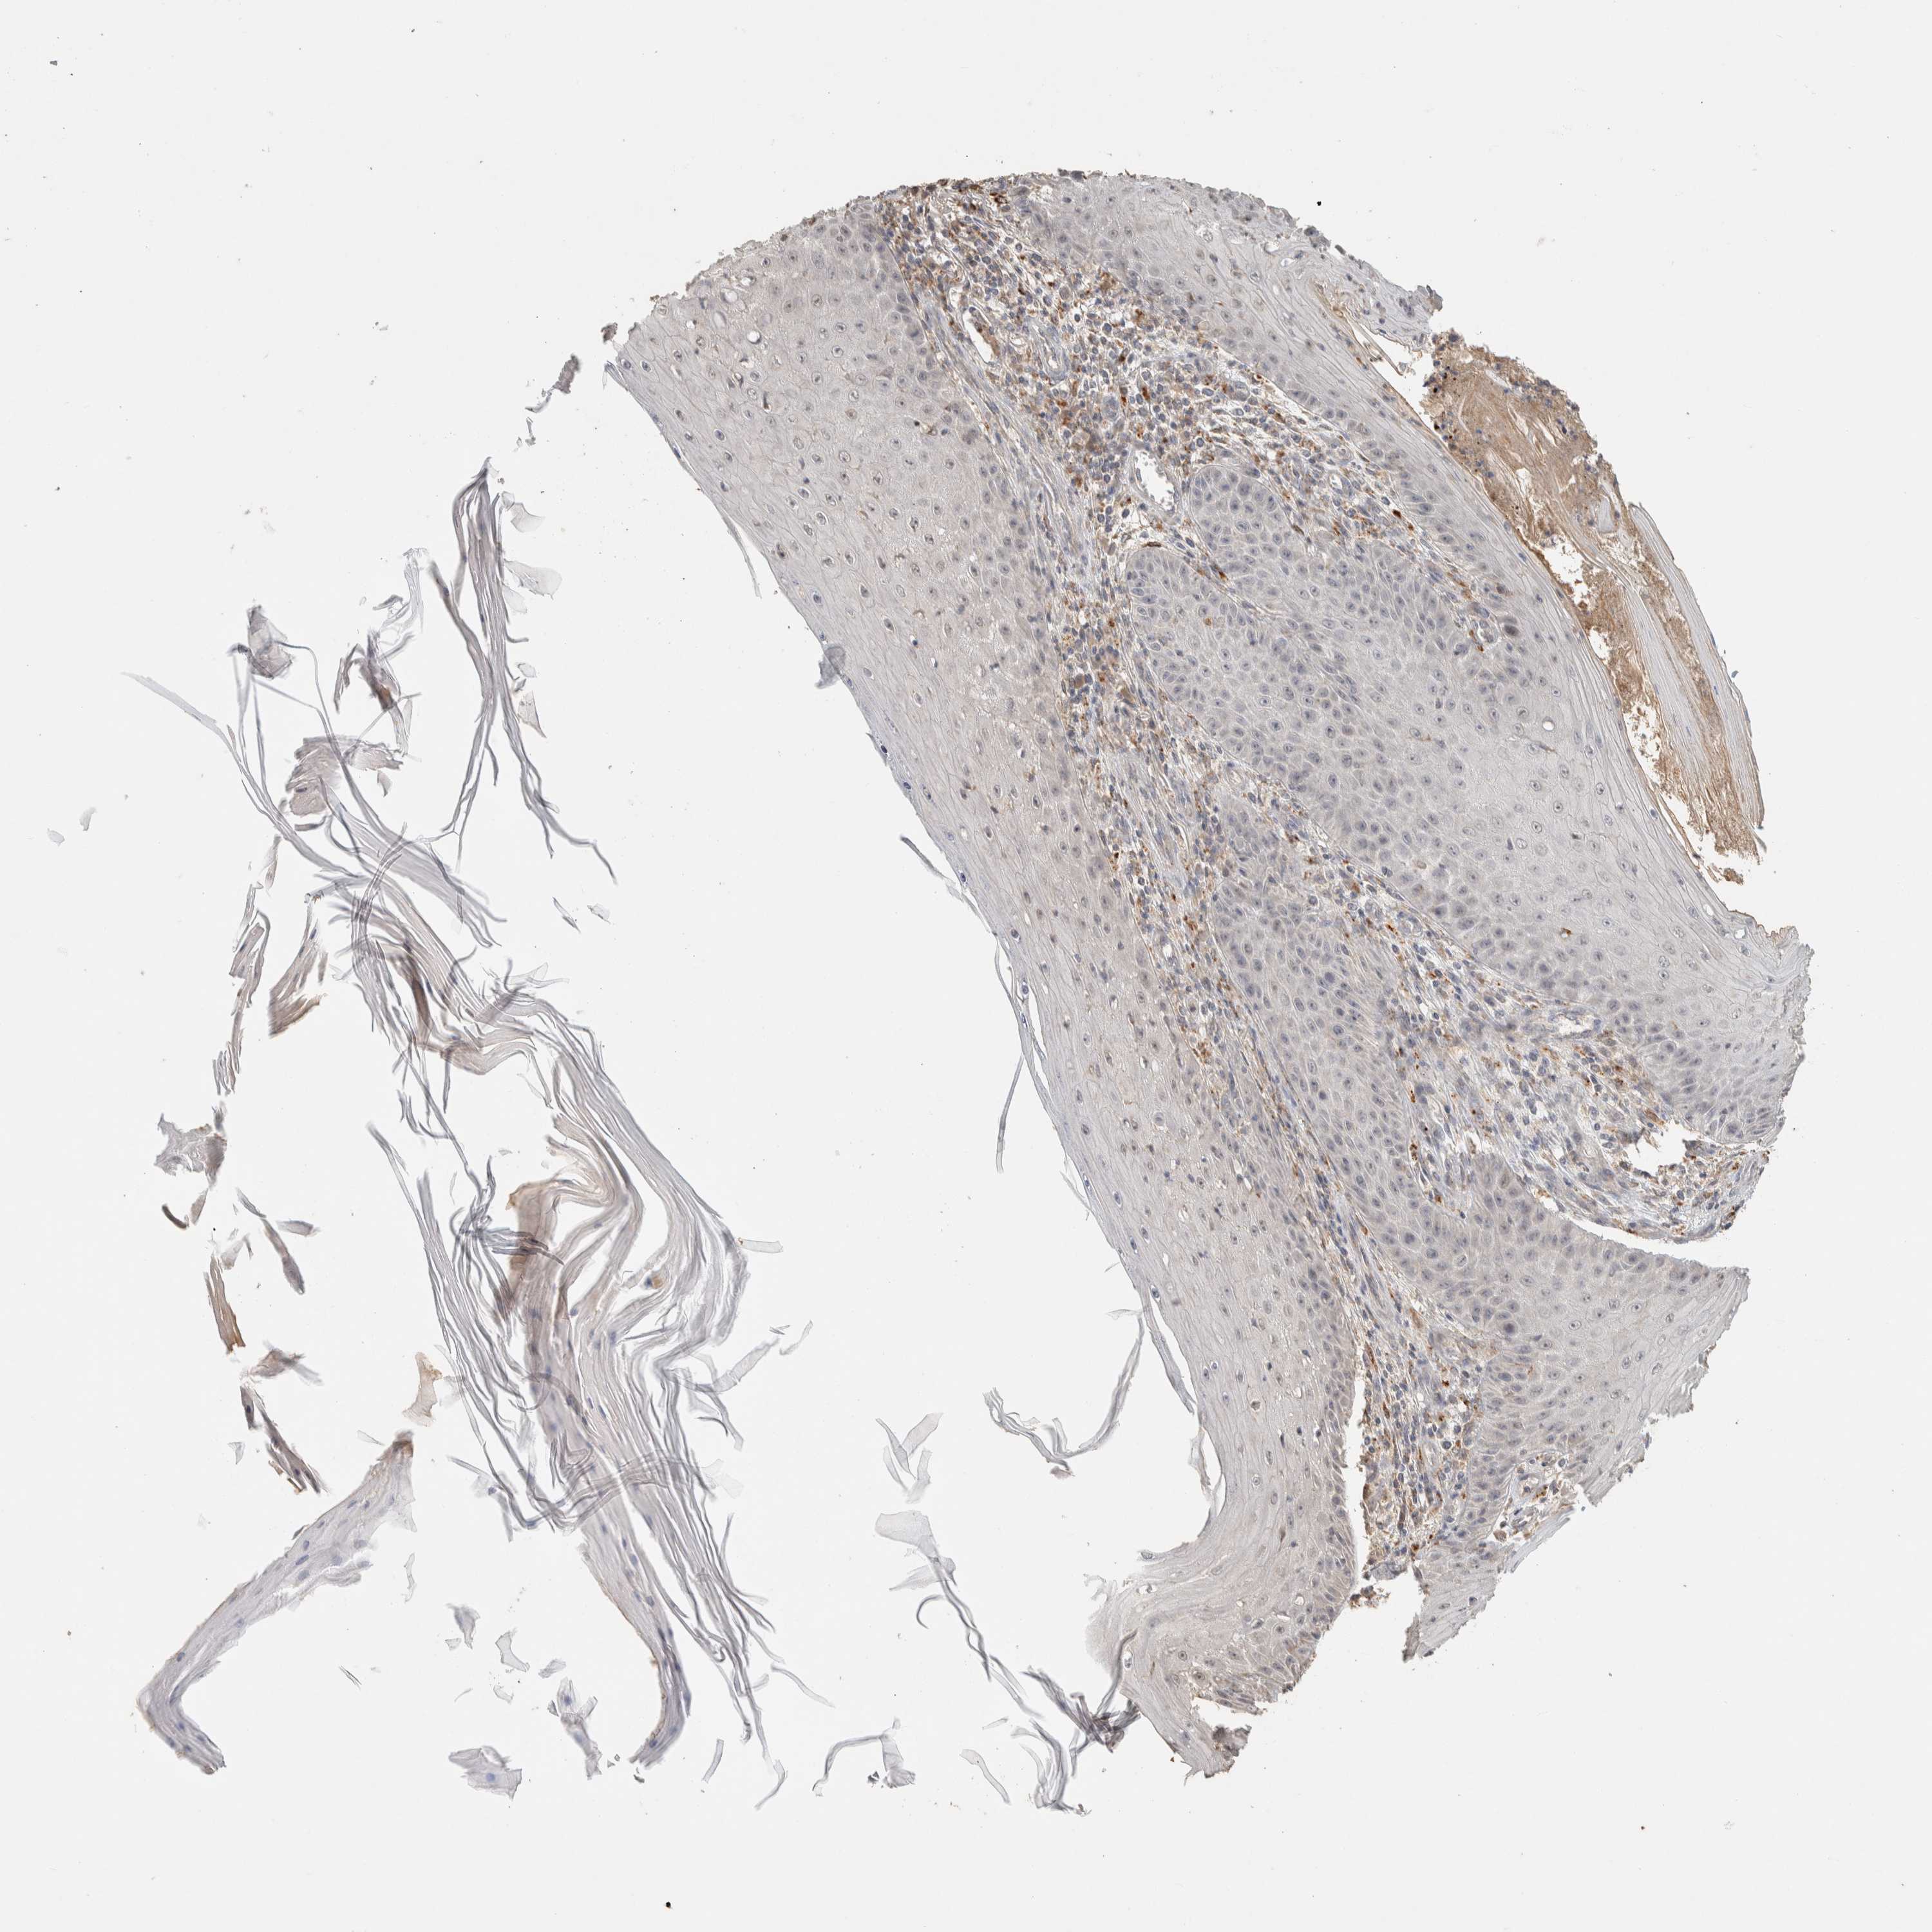

SKIN CANCER - Protein expressioni

A mouse-over function shows sample information and annotation data. Click on an image to view it in a full screen mode. Samples can be filtered based on level of antibody staining by selecting one or several of the following categories: high, medium, low and not detected. The assay and annotation is described here.

Antibody stainingi

Antibody staining in the annotated cell types in the current human tissue is reported as not detected, low, medium, or high, based on conventional immunohistochemistry profiling in selected tissues. This score is based on the combination of the staining intensity and fraction of stained cells.

Each image is clickable and will lead to virtual microscopy that enables deeper exploration of all samples and also displays staining intensity scores, fraction scores and subcellular localization as well as patient and tissue information for each sample.

Antibody HPA022824

Staining

High

Medium

Low

Not detected

Intensity

Strong

Moderate

Weak

Negative

Quantity

>75%

75%-25%

<25%

None

Location

Nuclear

Cytoplasmic/membranous

Cytoplasmic/membranous,nuclear

Squamous cell carcinoma, NOS